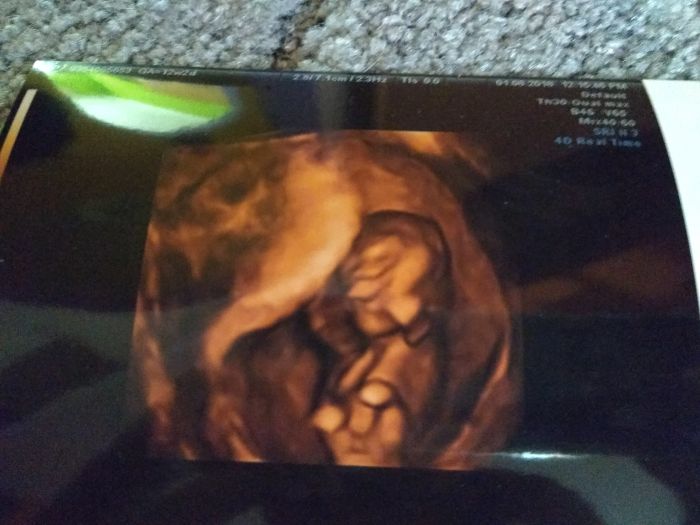

Screening dopadl výborně krev negativní i ultrazvuk v pořádku akorát jsme museli prďolkou budit

Jee to je krásná fotka,moc gratuluju!